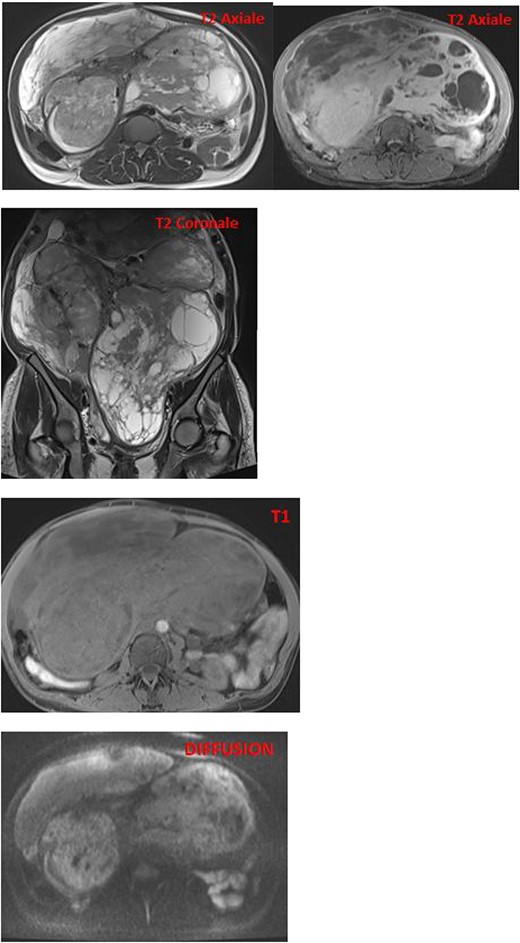

MRI images reveal an enlarged uterus with multiple myometrial formations exhibiting intermediate signal on T1 and T2, encompassing regions of hyperintensity on T2 and hypointensity on T1, enhanced homogeneously compared with the myometrium and without diffusion restriction, the most characteristic ones are classified as FIGO 6, FIGO 7, and FIGO 2–5, suggesting uterine leiomyomatosis with cystic degeneration.

The pathological and immunohistochemical examination suggested a smooth muscle mesenchymal tumor without signs of malignancy, raising the possibility of disseminated intravascular leiomyomatosis or a BML (Figs 4 and 5). The thoracic computed tomography (CT) indicated the presence of a mass in the inferior vena cava extending into the right atrium. Magnetic resonance imaging (MRI) confirmed uterine leiomyomatosis (Fig. 3). This explains the origin of the mass in the right atrium.

CT and MRI are crucial for determining the size and shape of the uterus (Figs 2 and 3), confirming the myometrial origin of the mass, and specifying the extent of vascular involvement. This classification distinguishes four grades [1]:

On MRI, the appearance of endovascular material depends on the quantity of smooth muscle cells and fibrous tissue. Generally, it exhibits low to intermediate signal on T1 and low signal on T2 [6] (Fig. 2).